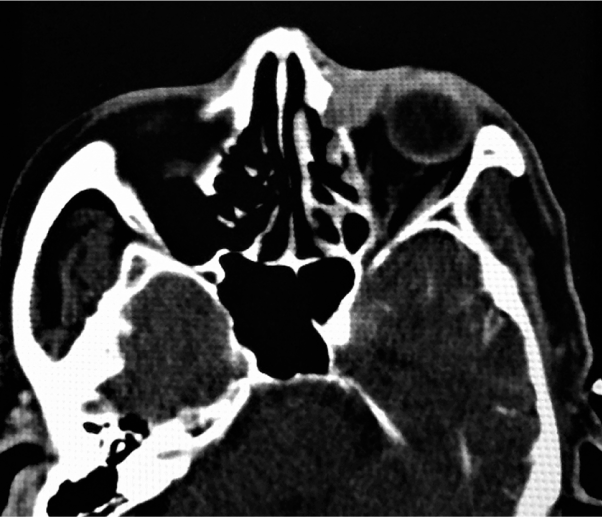

A 68-year-old-man was referred to our hospital with a hard mass in the left medial canthus and tearing. He had been diagnosed with maxillary sinus cancer at the age of 40 years and received chemoradiotherapy followed by partial maxillectomy at that time. He had also undergone coronary artery bypass surgery. Physical examination revealed a firm and fixed mass in the left internal canthus. An otolaryngologic rigid nasal/sinus endoscopy showed a firm mass under the normal-appearing mucosa just in front of the uncinate process (Figure 4A). Transnasal biopsy revealed moderately differentiated squamous cell carcinoma that was considered to be a radiation-induced cancer. A sinus CT demonstrated a massively enlarged left lacrimal sac with bone loss. There was also extension of the mass into the orbit (Figure 4B). The patient’s visual acuity was 20/20 and 20/20.

Figure 4. A firm mass under the normal-appearing mucosa just in front of the uncinate process [Figure 4A] CT scan showing an enhanced enlarged left lacrimal sac with bone loss. The enhanced mass extended into the orbit [Figure4B].